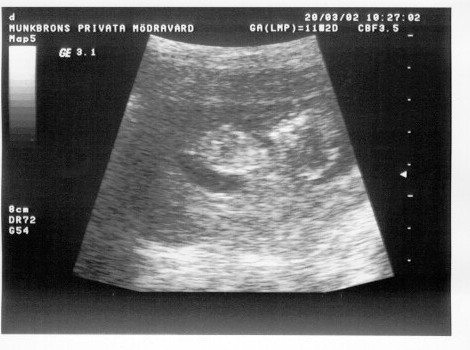

Ultra pictures

Start Uppåt Ett barn upptäcks Mage Ultra pictures

Well, bilderna är bara från vecka tolv men ändå.

Det är så vackert!!